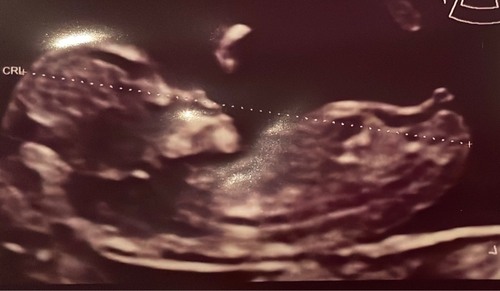

Wat denken jullie. Een meisje of een jongetje in juli? Echo is 13+2 dagen � ...

Ik neig naar een jongen!